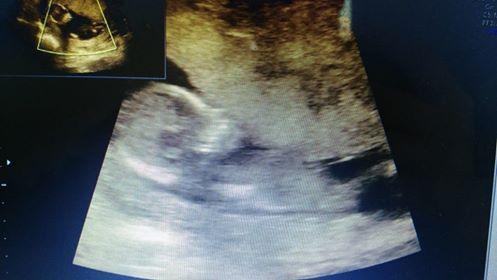

@simi1510 miminko je krásné 😘4 dny nehrají roli, taky mi je na ultrazvuku odecetli a teď na screeningu zase pricetli 🙂